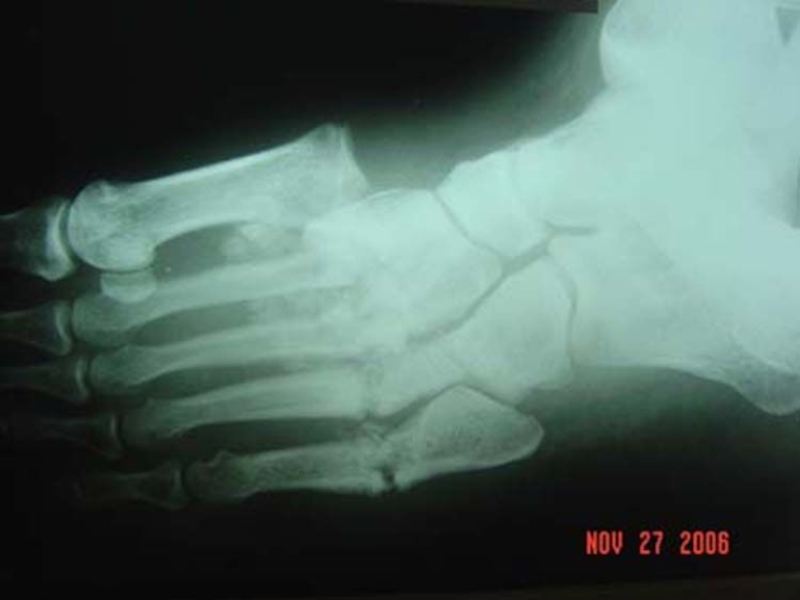

Слайд 30Диабетическая стопа

Диабетическая стопа — поражение стоп больного сахарным диабетом в виде

гнойно-некротических процессов, язв и костно-суставных поражений, возникающее на фоне изменения периферических нервов, сосудов, кожи и мягких тканей, костей и суставов. Является основной причиной ампутаций у больных сахарным диабетом.